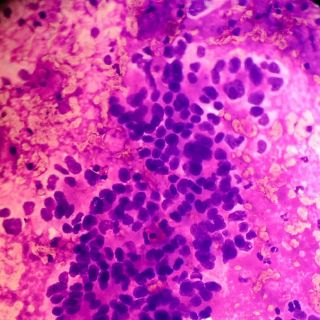

¿Qué es el adenocarcinoma de páncreas?

Ernesto Sánchez Forgach, cirujano oncólogo explicó a El Universal que un adenocarcinoma de páncreas “es un tumor que se desarrolla en este órgano que se encuentra en el retroperitoneo y se encarga de producir insulina y otras hormonas utilizadas por el cuerpo para la digestión”.

Detalló que este tipo de tumores no son altamente frecuentes y que lamentablemente en la mayoría de los casos se detecta en etapas avanzadas; “porque crece silenciosamente hacia una cavidad y los primeros síntomas suceden cuando el tumor ya está grande o cuando ya dio metástasis hacia el hígado o la vía biliar o por obstrucción de la vía biliar”.